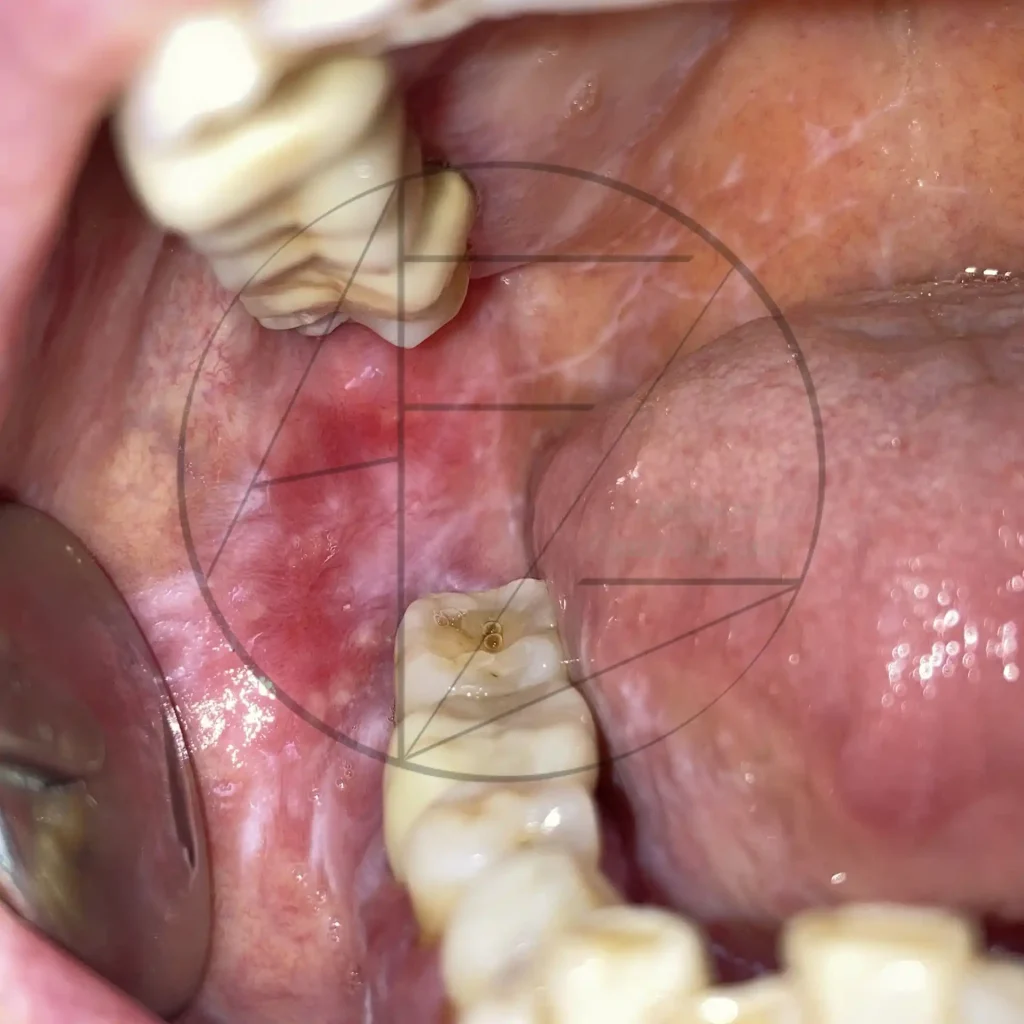

Liquen

Enfermedades ampollares